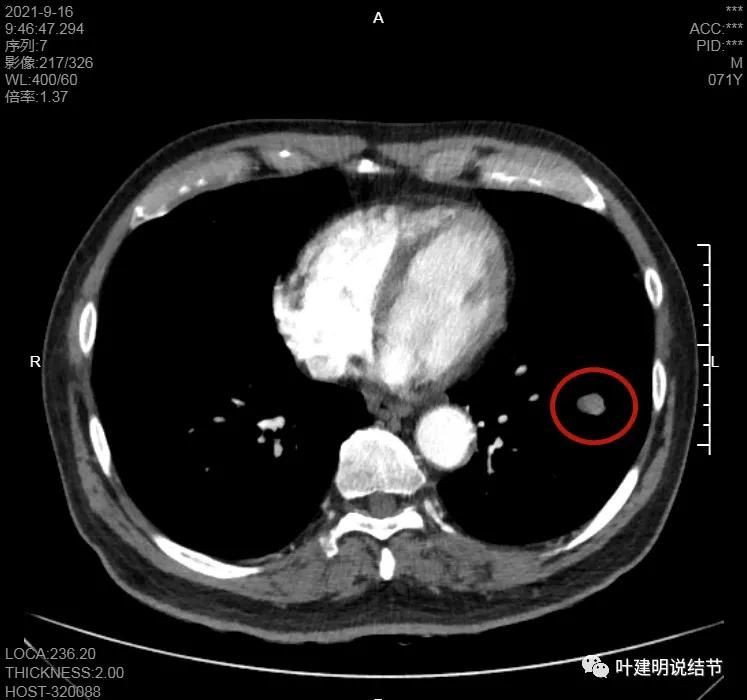

纵隔窗上也是很光滑的,据CT报告其强化也不明显:

左下病灶在增强CT中强化不明显,但有肺门区肿大淋巴结,而且近3厘米大。同事叫我看片子的时候,本来只先看左下病灶处,以为是良性结节。但翻到肺门区,发现有如此大的肿大淋巴结,那这个原发灶则肯定是恶性的了!我们先来看纵隔窗的淋巴结情况:

主动脉弓下有淋巴结,但不大

隆突下未见明显肿大淋巴结